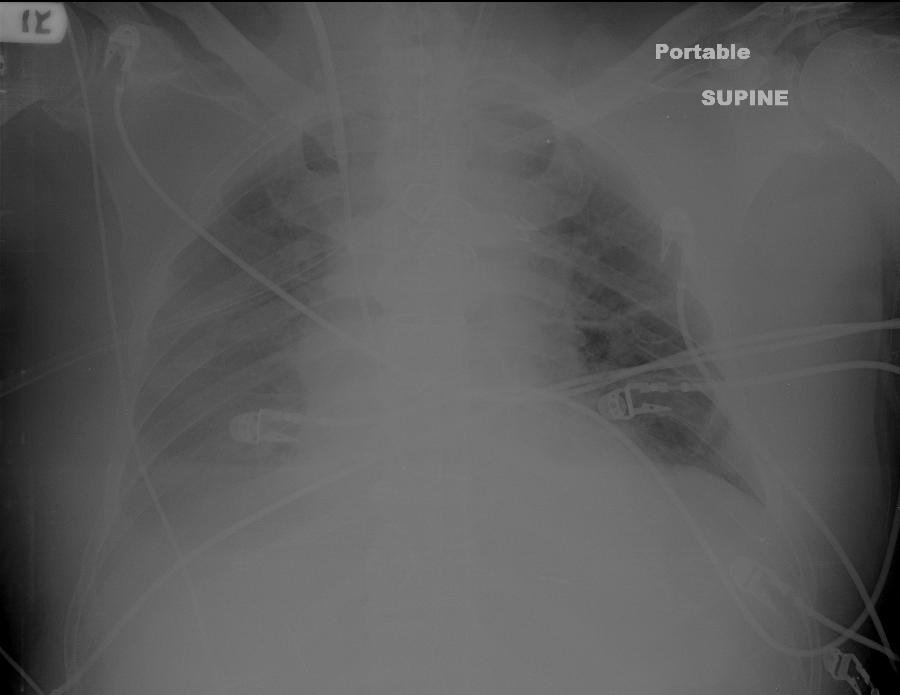

| IABP: Positioning with CXRGoal is placement of IABP tip 1-2 cm distal to SCA takeoff

As, unlike with echo, this position cannot be directly visualized, the radio-opaque marker on the tip of the IABP (which is beyond the balloon) is positioned using radiographic landmarks in a properly exposed chest film of a properly positioned patient.The CXR on the left shows a common ICU x-ray: Poorly exposed, patient not properly positioned (though pretty good). With digital images, it is usually possible to adjust the contrast so that the essential landmarks can be seen. If you cannot see what you need, get the image re-shot. Here the IABP is too low, though you would be hard pressed to identify this.The image to the right is a better exposure for lines, but it is difficult to precisely identify the  radiographic landmarks for IABP placement. Arrow points to IABP tip marker (vertical, white, ~2 cm long). Placement is still too low.Radiographic landmarks for correct position  vary somewhat by author. The most common is that the IABP tip marker should be 2cm below the top of the aortic knob; second most common is that the tip should be in the 2nd or 3rd intercostal space anteriorly. Either, or both, of these landmarks may be difficult to visualize in the typical ICU patient who needs a balloon. Fortunately, most of these patients have a PAC in place. My suggestion is that if the other landmarks are difficult to see, simply place the tip of the IABP 1-2cm superior to the highest point on the PAC as it passes through the right (usually) or left PA.The anatomic drawing from Gray's Anatomy makes this relationship clear. If seen, the aortic knob is likely the best. If knob not visualized well, the PAC method is probably the next best. The interspace method suffers from the width of the interspace's, and from the large geometric change with changing patient position.Even if placed using fluoroscopic guidance, it is best that IABP position be documented with CXR. IABP position should be confirmed by CXR at least once a day, whenever it is repositioned, and whenever it might have accidentally been moved, as malpositioning can kill the brain, bowel, kidneys, or patient. |